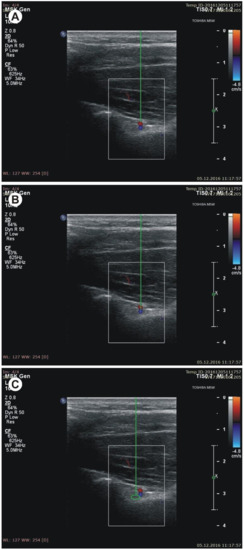

- the diameter of the suprascapular artery (Figure 3A)

- the diameter of the suprascapular vein (Figure 3B)

- the diameter of the suprascapular nerve (Figure 3C)